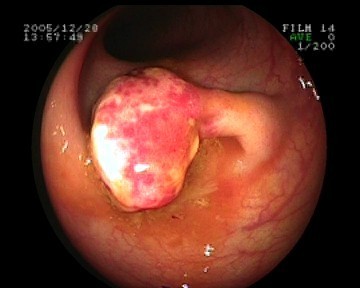

Coloskopie - kleiner flacher Polyp (Frühkarzinom)